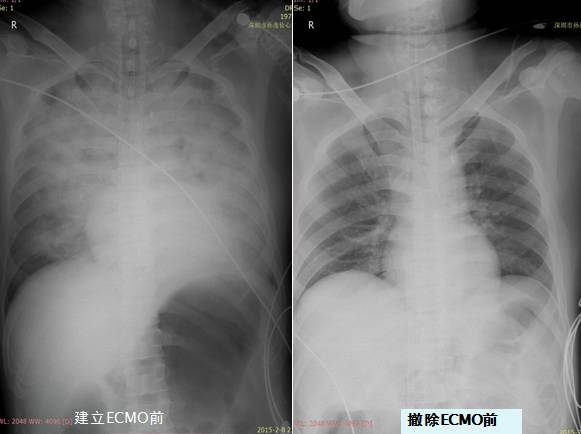

胸片

急性

肺水肿

ECMO

ECMO建立后生命体征变